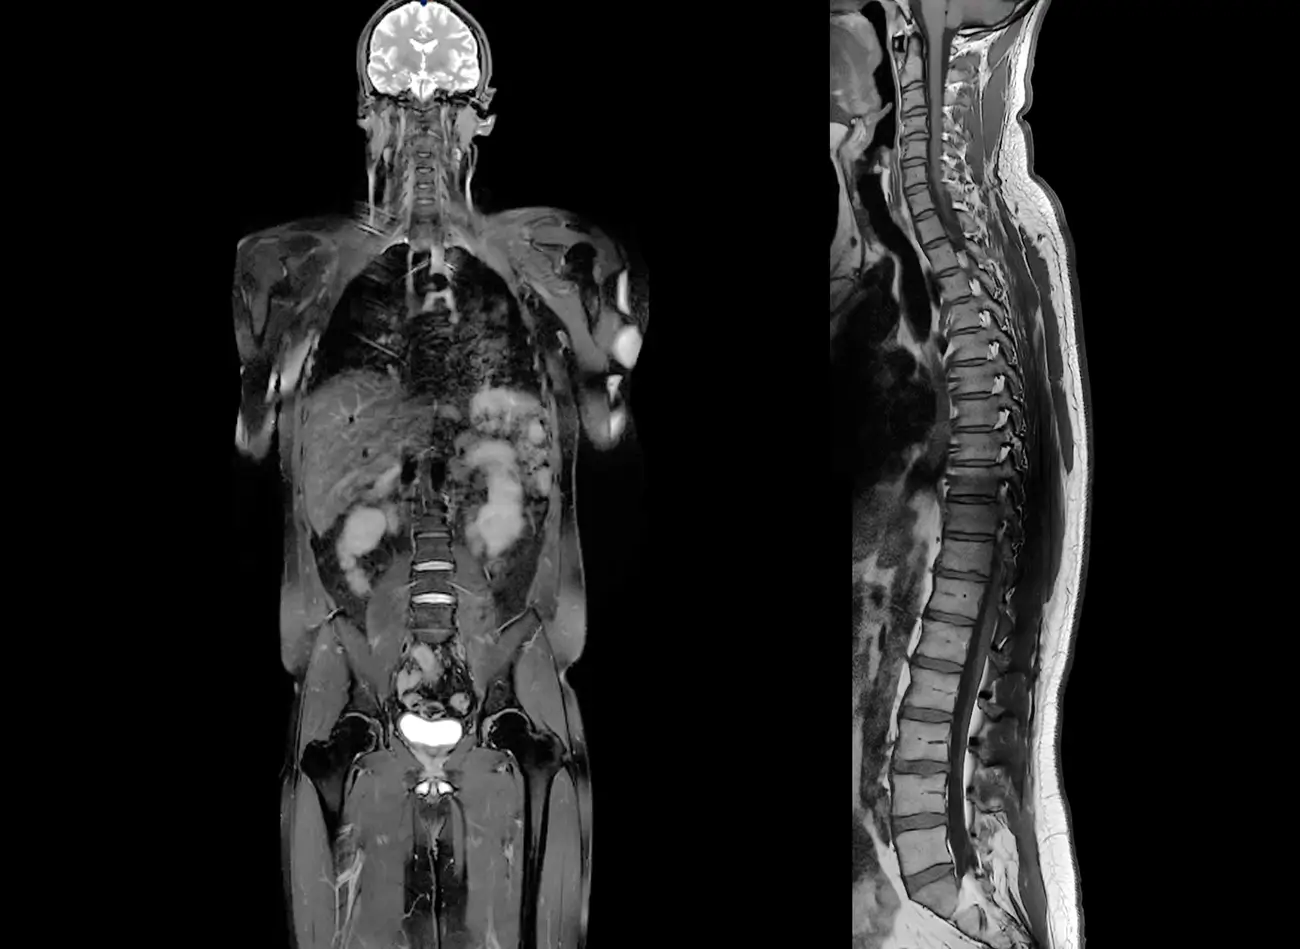

This non-invasive, multi-dimensional screening view of the body using magnetic resonance imaging (MRI) can be used to evaluate possible conditions before they become a concern, allowing you to better manage your health. State-of-the-art whole body imaging may lead to early diagnosis, allowing you to achieve peace of mind and better manage your health.

Whole body imaging (WBI) takes approximately one hour and evaluates:

• The brain, including its major blood vessels.

• The spine and spinal cord.

• The major organs of the body, including the salivary and thyroid glands, lymphatic system, liver, gallbladder, biliary system, pancreas, spleen, adrenal glands, kidneys, bladder, uterus, ovaries, prostate and testes.

• The lungs and bowel are not optimally assessed with MRI but supplemental low-dose CT of the lungs and colon can be obtained as an add-on.

• Dedicated evaluation of the major joints of the body is also available as an add-on.

Whole body imaging has the ability to detect hundreds of different conditions including many types of early-stage cancer, multiple sclerosis, brain aneurysms, narrowing of the arteries, ischemic injury, vascular malformations, various metabolic disorders, disc herniations, endometriosis, neurodegenerative disorders and spinal degeneration.

This non-invasive, multi-dimensional screening view of the body using magnetic resonance imaging (MRI) can be used to evaluate possible conditions before they become a concern, allowing you to better manage your health. State-of-the-art whole-body imaging may lead to early diagnosis, allowing you to achieve peace of mind and better manage your health.

The brain, including its major blood vessels.

The spine and spinal cord.

The major organs of the body, including the salivary and thyroid glands, lymphatic system, liver, gallbladder, biliary system, pancreas, spleen, adrenal glands, kidneys, bladder, uterus, ovaries, prostate and testes.

The lungs and bowel are not optimally assessed with MRI but supplemental low-dose CT of the lungs and colon can be obtained as an add-on.

Dedicated evaluation of the major joints of the body is also available as an add-on.

Whole body imaging may help detect various forms of cancer, multiple sclerosis, brain aneurysms, narrowing of the arteries, ischemic injury, masses, vascular malformations, metabolic disorders, disc herniations, and spinal degeneration.